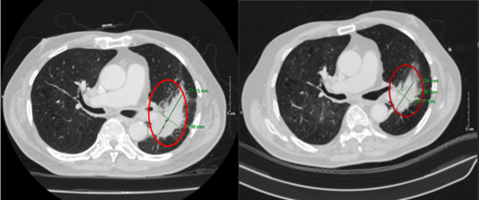

Hình 7.1: Cắt lớp vi tính ngực ở cửa sổ nhu mô

Hình 7.2: Hình ảnh cắt lớp vi tính ngực ở cửa sổ trung thất

Kết luận: Hình ảnh chụp cắt lớp vi tính ngực: sau 6 đợt điều trị khối u (vòng tròn đỏ) giảm kích thước từ 72x41mm (bên trái) xuống còn 43x28mm (bên phải)

Hình 8: Hình ảnh CT ngực: Sau 6 đợt điều trị hạch trung thất giảm kích thước từ 11x18mm trước điều trị (mũi tên vàng) xuống còn 8x10mm sau điều trị (mũi tên đỏ)